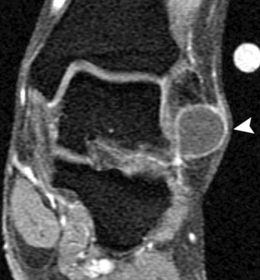

| What disease is this? What does the arrow indicate? | Rheumatoid arthritis. Arrow = Bone erosion secondary to inflammation of retrocalcaneal bursa. |